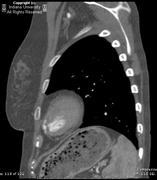

Post thoracic aortic surgery findings